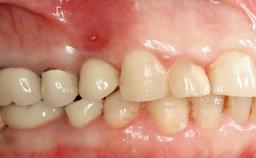

This case describes the ongoing management of a 64-year-old healthy, non-smoking female patient with erosive oral lichen planus (OLP) affecting the gingivae and the buccal and lingual mucosa. The peri-implant mucosa was also affected subsequent to implant placement. The patient had osseointegrated implants (four in the maxilla, four in the mandible) placed following extraction of hopeless teeth and a healing period. The patient had a history of OLP prior to implant placement and had been referred to an oral-medicine specialist for definitive diagnosis and treatment. She exhibited generalized oral mucosal involvement. Following a clinical assessment, biopsy, and blood tests, she was treated with topical corticosteroids. Systemic prednisolone was reserved for severe flare-ups. Amphotericin lozenges were used in combination with corticosteroid treatment to prevent the development of oral candidiasis.